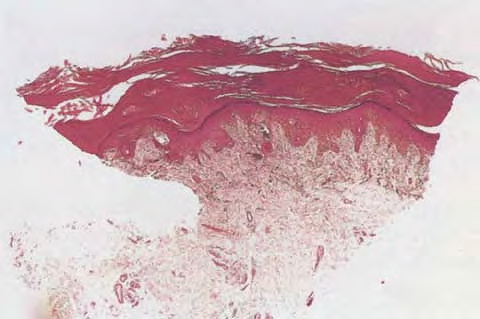

Acral melanoma =ميلانوم النهايات